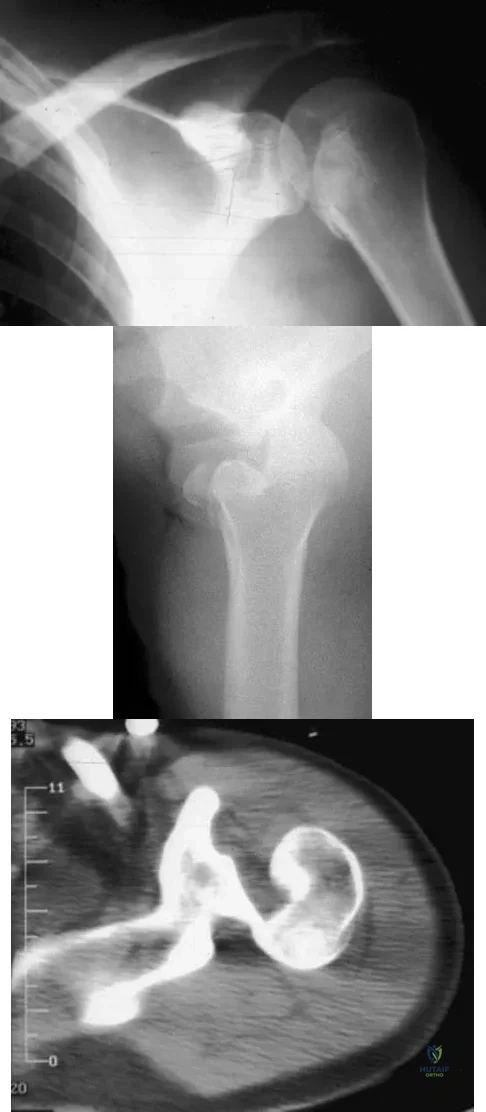

Figures 11a and 11b show the AP and lateral radiographs of a 32-year-old patient on hemodialysis who has increasing elbow pain and a visibly growing mass over the extensor surface. Figure 11c shows the photomicrograph of the biopsy specimen. What is the most likely diagnosis?

Figures 11a and 11b show the AP and lateral radiographs of a 32-year-old patient on hemodialysis who has increasing elbow pain and a visibly growing mass over the extensor surface. Figure 11c shows the photomicrograph of the biopsy specimen. What is the most likely diagnosis?

Following a fall from a height of 5 feet, a patient reports pain along the lateral border of the foot. The CT scan shown in Figure 54 indicates what pathology?

Figures 28a and 28b show AP and lateral radiographs of the knee. Based on these findings, which of the following structures has most likely been injured?